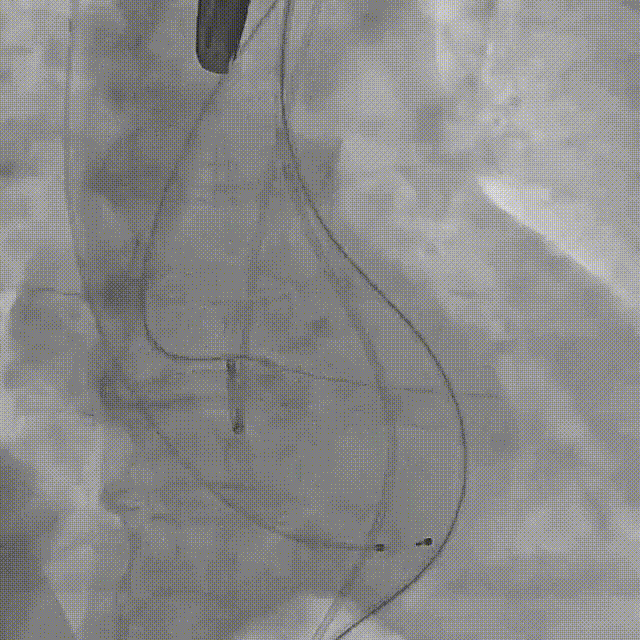

术中影像

直头导丝跨瓣

球囊预扩

释放

后扩前

后扩

最终工作位置

术中及术后未出现相关并发症,瓣膜植入位置完美,患者症状得到明显改善,手术圆满完成。